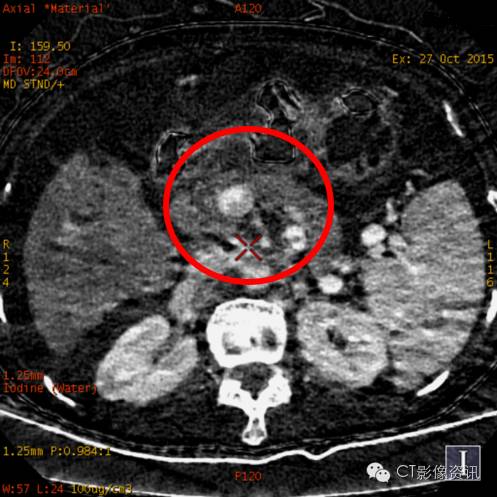

癌栓定量分析

动脉期碘基值(9.5~12.88)

栓子定量分析

门静脉期碘基值(31~36)